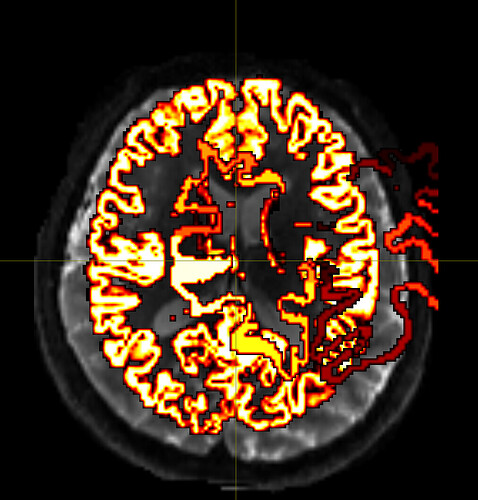

Despite extensive tuning, the final transformed atlas (DKT308_parc.mif) consistently exhibits significant bleeding (invasion) into the white matter (WM) in high-curvature sulcal regions.

I diagnosed this as over-regularization in the FNIRT process (the algorithm prioritizes smoothness over anatomical accuracy).

Visual Evidence

(Please insert the image showing the atlas bleeding into the white matter here)